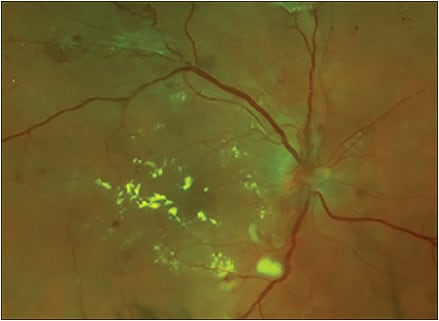

Like radiology, ophthalmology is another field in which the diagnosis can often be made based on visualization of the underlying pathology. This is especially true for diseases that affect the retina, such as diabetic retinopathy (Figure).

Figure. Clinical features of DR may include hemorrhages, hard exudates, cotton wool spots, and/or neovascularization.

In the case of DR, nearly all of the information required to make a decision regarding diagnosis, staging of the disease, and treatment can be gleaned via a thorough inspection of the retina. Now that it is possible to obtain high-quality images of the retina for later review by an expert reader (a “store and forward” method of telemedicine), DR has become a model ophthalmic disease for a telemedicine-based approach to reducing preventable blindness.